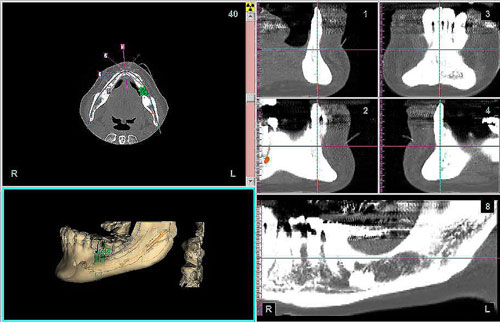

Mientras dichos movimientos ortopédicos se producen (período que supondrá otros seis meses), estudiamos los actos quirúrgicos a realizar en los cuatro implantes que pondremos. De acuerdo al estudio Desatascan realizado observamos tres situaciones diferentes: 1º-El Primer Molar Inferior Izquierdo, lo instalamos mediante Cirugía Minimamente Invasiva , con la aplicación de una Férula Quirúrgica Obtenida de los datos del scanner tratados con un programa de CMI (Cirugía Minimamente Invasiva), previa prueba en un modelo estereolitográfico, ya que la altura ósea era apenas de 9 mm. 2º- El Primer Molar Superior Derecho, se implantará mediante una ligera Elevación Atraumática (Trans alveolar) de Seno una vez logrado el espacio mesio distal necesario. 3º- El Incisivo Central Superior Derecho ausente, cuenta con un sustrato óseo prácticamente inexistente. El espesor de la tabla era de menos de 2 mm. Los caminos posibles a seguir para contar con una Rehabilitación de piezas independientes son dos: Optamos por esta segunda opción por ser menos cruenta y no necesitar de una zona dadora. Técnica esta que pondremos en práctica en dos etapas diferidas: 1º-Incisión horizontal palatinizada, incisiones peri rodetes gingivales e incisiones de descarga. Dilatación que comenzamos con dos incisiones de descarga sobre la cortical vestibular realizadas con disco. y el comienzo de la dilatación propiamente dicha mediante una hoja de bisturí, para luego seguir con un periostótomo . Recién después de alcanzada una cierta separación de la cortical vestibular de la palatina, empezamos con los dilatadores roscados. En este punto podríamos haber utilizado sin riesgos un Implante de 3,8 mm de diámetro, pero a fin de mejorar la estética del pilar emergente decidimos rellenar con material osteoconductor y osteoinductor (BiOss) y cubrir mediante membrana reabsorvible ( Bio Guide). 2º-Implantación seis meses después. Mientras se van cumpliendo los tiempos antes mencionados, y comprobamos reiteradamente la funcionalidad de la oclusión con los provisorios, tomamos impresiones definitivas y construimos primero el maxilar inferior, para definir en primer término la porción inferior de la Guía Anterior., y a nivel posterior Curvas y Microplanos. Para luego realizar los cuadrantes premolar- molar del superior: La espera de la regeneración ósea y sus tiempos pertinentes, más la espera de los tiempos de la implantación, nos obligaron a modificar las etapas del protocolo D.AT.O de manera de mantener la –D- mediante el sector superior de la GA. en provisorios, mientras fuimos resolviendo en forma definitiva los demás sectores. Ya pasados los meses necesarios para recrear un hueso adecuado en el área del Incisivo Superior Derecho, procedemos a resolver la implantación de dicha zona, observando que todo el esfuerzo dedicado al mismo había sido inútil, ya que la formación de hueso se produjo minimamente. Cuatro meses después tomamos impresiones del sector Antero Superior de la Guía Anterior, incluyendo el arrastre de un transfer . Seguimos modelando la encía con un nuevo juego de provisorios. Y se construye entonces el sector superior de la Guía Anterior. Se efectúa un control radiográfico a los 6 meses. Se ha intentado mostrar en esta Rehabilitación, que a pesar de las distintas circunstancias de cada paciente, siempre debemos tener en cuenta la necesidad de ejercer la DESOCLUSIÓN del caso como prioridad número uno, para luego perseguir la ALINEACIÓN TRIDIMENSIONAL de las arcadas y obtener así una OCLUSIÓN equilibrada. D.AT.O. ES EL PROTOCOLO QUE DEBEMOS SEGUIR EN TODA REHABILITACIÓN. BIBLIOGRAFÍA 1)William Mc Horris,B.S.,D.D.S. Oclusión. Con especial énfasis sobre :El rol funcional y parafuncional de los dientes anteriores. 2)Von Spee , Craff(Anatomista alemán, describió la curva de compensación de la articulación de molares y premolares).CURVA DE SPEE 1.89 3)Stuart,D.”Some aspects of the inervation teeth.”Procedings of Royal Society of Medicine.20:1675,19274)Muhleman,H. y Savdir,S”Tooth movility-its causes and significance”Journal of Periodontology ,36:153,Marzo ,Abril,1965. 4)Muhleman,H. Y Savdir,S”Toothmovility its causes and significance” Journal of Periodontology,36:153,marzo,abril,1965. 5-Oclusión y Diagnóstico en Rehabilitación Oral. 6-Anatomia Odontológica. 7-A contribution to the study of the movementes of the mandible. 8-Celenza F.W, Nadeskin J.F.,Oclusión.Situación actual. 9-D´Amico 10-Dawson P.E. 11-Huffman –Regenos. 12-Hobo S.-Takayama H.A. 13-Lucia V.O 14-Mc Horris. 15-Mc Horris. 16-Stuart C. 17-Vartan Veshnilian 18-Alvarez Cantoni H. AUTOR:Ratificación del Protocolo en Rehabilitación Bucal a pesar de las incidencias propias de cada caso clínico. A propósito de un caso.

Tridimencionalización mediante implatemetric y ensayo de colocación de implantes

Tridimencionalización mediante implatemetric y ensayo de colocación de implantes

Perforación de prueba en mod. esteorlit.